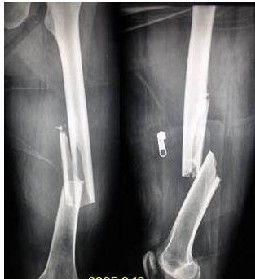

股骨幹骨折 1.懸吊牽引法:用於4-5歲以內兒童。將二下肢用皮膚牽引向上懸吊,重量約1-2公斤,要保持臀部離開床面,利用體重作對抗牽引。3~4周經X線照片有骨痂形成後,去掉牽引,開始在床上活動患肢,5-6周后負重。對兒童股骨幹骨折要求對線良好,對位要求達功復位即可,不強求解剖復位。如成角不超過10°重疊不超過2厘米,以後功能一般不受影響。在牽引時,除保持臀部離開床面外,並應注意觀察足部的血液循環及包紮的鬆緊程度,及時調整,以防足趾缺血壞死。股骨幹骨折

2.動滑車皮膚牽引法(羅索氏Russell牽引法):適用於5歲至12歲兒童。在膝下放軟枕使膝部屈曲,用寬布帶在膕部向上牽引,同時小腿行皮膚牽引,使兩個方向的合力與股骨幹縱軸成一直線,合力的牽引力為牽引重力的二倍。有時亦可將患肢放在托馬氏夾板及Pearson氏連線架上,進行滑動牽引。牽引前可行手法復位,或利用牽引復位。

股骨幹骨折 3.平衡牽引法:用於青少年及成人股骨幹骨折。在脛骨結節處穿針,如有傷口可在股骨髁部穿針(克氏針或斯氏針)。患肢安放在托馬氏夾架上,作平衡牽引,有復位及固定兩種作用。可先手法復位小夾板維持,然後,用維持重量持續牽引(維持重量為體重1/2),或直接用牽引復位(復位重量為體重1/7)復位後改為維持重量。根據骨折移位情況決定肢體位置:上1/3骨折應屈髖40-50°,外展約20°,適當屈曲膝關節;中1/3骨折屈髖屈膝約20°,並按成角情況調整外展角度;下1/3骨折時,膝部屈曲約60-80°,以便腓腸肌鬆弛,糾正遠側骨端向後移位。牽引後24-48小時要進行床邊X線照片,了解骨折對位情況,同時每日多次測量骨端肢體長度,並加以記錄,以資參考。要根據X線照片及測量情況,及時調整肢體位置,牽引重量和夾板。要防止牽引不夠或牽引過度。在牽引時還應注意觀察穿針部位有無感染,以及肢體保溫,並教會病人鍛鍊軀體,上肢、患肢關節和肌肉的方法。使用平衡牽引,病人較舒適,牽引期間能活動髖、膝和踝關節,擦澡和大小便較方法。一般牽引4-6周,經X線照片有骨痂形成後,可改用髖人字石膏固定4-8周。在牽引中可同時套用小夾板固定,糾正成角。去除牽引後也可用小夾板外固定,但要經常複查以防骨折移位或成角。